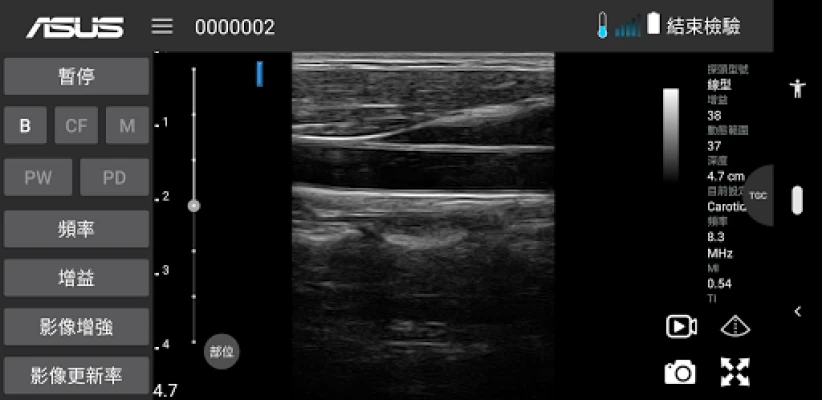

ASUS Portable Ultrasound is a wireless, handheld, pocket-sized imaging tool.

This flexible and feasible APP supports reliable and dependable images for diverse scenarios.